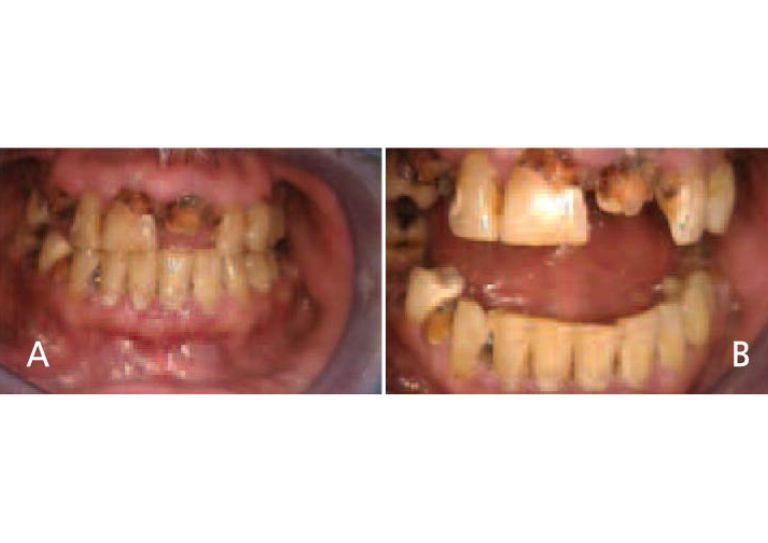

Oral manifestations in the advanced states of methamphetamine abuse include A) teeth broken off at the gingival margin; and B) grayish-brown dentition with enamel that is reduced to a soft leathery texture, along with gingivitis and acute periodontitis.